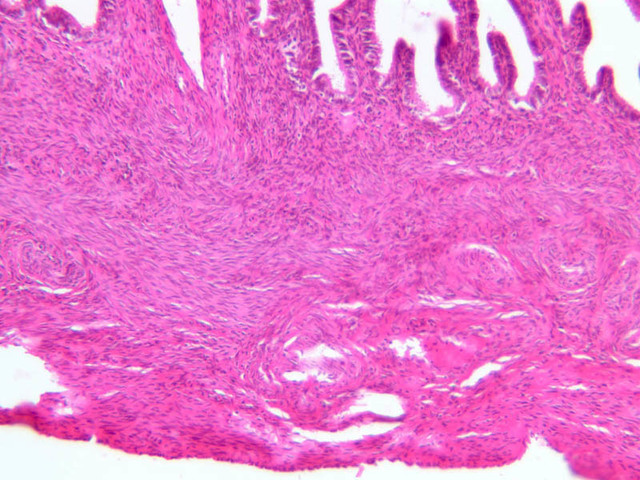

The uterus is a pear-shaped muscular organ, somewhat flattened from front to back. The expanded upper portion is referred to as the fundus, while its lower part, which protrudes into the vagina, is called the cervix. The lumen of the uterus is slit-like and is in communication with that of the uterine tubes (B-97, monkey uterus [1x, 1x, 1x, 1x]). The wall of the uterus consists of three layers: perimetrium, myometrium, and endometrium (B-97 [1x, 1x-labeled] [1x, 1x, 1x]; B-100 [1x, 1x]). The perimetrium is peritoneum which covers the uterus, but is lacking in the posterocaudal third below the peritoneal reflection (B-97 [2.5x, 10x, 20x, 40x]). The myometrium is the very thick middle layer consisting of bundles of smooth muscle cells arranged into several interwoven layers (slide B-93 [1x-labeled, 2.5x] [1x, 2.5x] [1x, 2.5x] [2.5x, 10x, 20x, 40x]). The endometrium is the innermost layer and is a glandular mucosa (B-97 [2.5x, 10x, 20x] [2.5x, 10x, 20x] [2.5x, 10x, 20x, 40x]). It consists of a surface epithelium which is invaginated into tubes called uterine glands. The glands penetrate into a very thick lamina propria referred to as the endometrial stroma. The surface epithelium is a mixture of ciliated and non-ciliated simple columnar cells, whereas the glandular epithelium consists mainly of non-ciliated secretory cells. The endometrial stroma has the appearance of a loose, rather cellular mesenchyme with numerous blood vessels.

The endometrium is subdivided into two main parts; the basalis and the functionalis (slide B-97). The basalis is deep, lying adjacent to the myometrium, it consists of stroma and the closed ends of the uterine glands and is not sloughed during menstruation. The functionalis is upper zone consisting of the remainder of the uterine glands with intervening stroma. It is lost during menstruation, but is replaced again with each menstrual cycle, by proliferation of the persisting elements in the basalis.

The menstrual cycle is a continuous series of events, dominated by the endocrine activity of the ovary, which repeats itself with a 28 day period. The endometrium participates by undergoing a series of structural changes which are roughly divided into three categories, the proliferative, secretory, and menstrual phases. These phases are listed below, examine each of the uterine slides and determine to which phase it belongs.